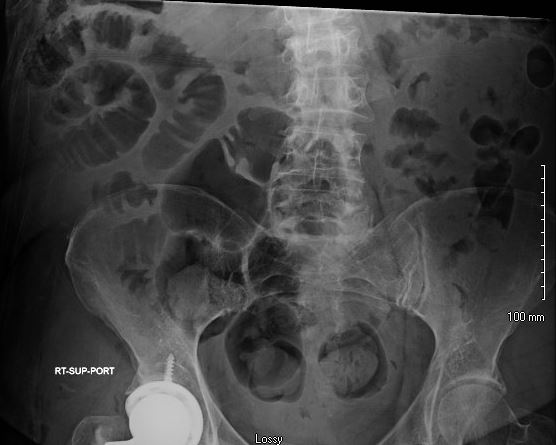

Case Presentation: A 53-year-old female with history of Roux-en-y bypass, hypertension, and type 2 diabetes mellitus presented to the emergency department following a mechanical fall. She was found to have a right femoral neck fracture and was admitted for surgical repair. There were no apparent intraoperative complications. Upon arrival to the general care floor shortly after her surgery, she developed acute, severe abdominal pain and hypotension. Arterial blood gas demonstrated mild metabolic acidosis (pH: 7.26, pCO2: 41, bicarbonate: 18.5) and lactate of 0.8. The remainder of her labs (i.e., complete metabolic panel, complete blood count) were relatively unremarkable.Initial differential was broad, ranging from ischemic bowel injury related to anesthesia or cardiac event, small bowel obstruction, perforated gastric or duodenal ulceration, acute cholecystitis, acute colonic pseudo-obstruction, and propofol-induced pancreatitis. Stat abdominal x-ray revealed dilated bowel loops in the right hemipelvis, prompting a stat CT abdomen/pelvis with and without contrast. CT demonstrated an internal, likely Petersen type hernia with associated twisting of the mesentery and resultant severe small bowel mesenteric congestion, bowel wall thickening, and edema with decreased small bowel enhancement concerning for developing ischemia. Repeat venous blood gas showed a worsening pH (7.17) and increased lactate (2.1), consistent with developing ischemia.The patient underwent urgent laparoscopic surgery with general surgery. She was found to have herniation of her entire small bowel through the Petersen defect with resulting volvulus upon itself. Detorsion of the volvulus and reduction of the hernia through the Petersen defect was performed and the defect was closed. She then had an uneventful recovery.